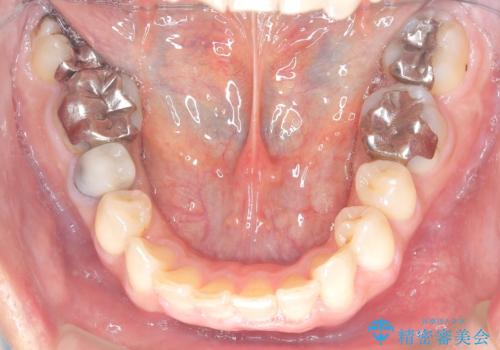

【遠心移動ワイヤー矯正】翼状捻転を治したい

- 前歯の捻れを主訴に来院されました。

顔貌の正中と上顎前歯の正中があっており、下顎は顎位が偏位している状態でした。

小臼歯を抜歯する治療計画も提案しましたが、

今回は患者さんの希望もあり非抜歯にて歯列拡大、遠心移動を行なってできる限り前歯を下げながら配列する治療を行いました。

上顎はリンガルアーチにて遠心移動を行うことで前歯を唇側傾斜させずに配列することができました。